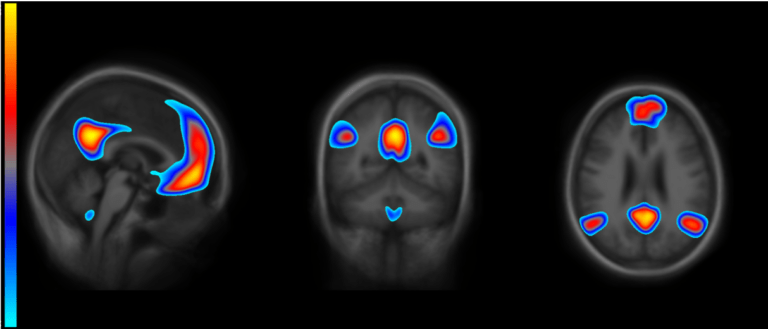

Toward a biological definition of alzheimer's disease in 2011, the national institute on aging and alzheimer's association created separate diagnostic recommendations for the preclinical, mild cognitive impairment, and dementia stages of alzheimer's disease. Earlier this year, the food and drug administration approved the drug aducanumab to treat alzheimer’s disease. Alzheimer's disease is the most common cause of dementia — a continuous decline in thinking, behavioral and social skills that affects a person's ability to function independently.